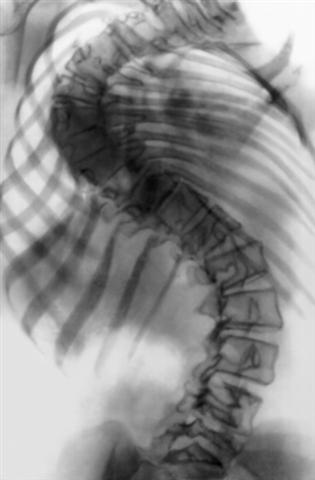

Рис. 18а). Рентгенограмма позвоночника (прямая проекция) при правостороннем грудном сколиозе IV степени до операции.